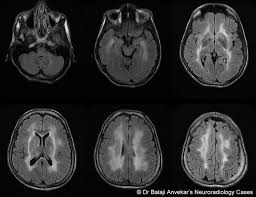

Neuromuscular Manifestations of Sjogrens syndrome Patients suffering from Sjogrens syndrome may develop a whole variety of neuromuscular complications. Additionally hyperintense T2 lesions on brain MRI may be present and can appear similar to lesions seen in multiple sclerosis. In addition Sjogrens syndrome may cause skin nose and vaginal dryness and may affect other organs of the body including the kidneys blood vessels lungs liver pancreas and brain.

Dr Balaji Anvekar Frcr Sjogren S Syndrome Mri Brain

Neuromuscular Manifestations of Sjogrens syndrome Patients suffering from Sjogrens syndrome may develop a whole variety of neuromuscular complications. The first is ichthyosis which is a buildup of skin to form a scale-like covering that causes dry skin and other problems. Primary Sjogrens symptoms and objective signs of ocular dryness with positive Schirmers test and positive Rose-Bengal or fluorescein staining of cornea and conjunctiva. Primary Sjogrens Syndrome symptoms are pure sensory neuropathy sensorimotor neuropathy neuronopathy cranial nerve involvement polyneuropathy mononeuritis multiplex and polyradiculoneuropathy. Additionally hyperintense T2 lesions on brain MRI may be present and can appear similar to lesions seen in multiple sclerosis. Sjögrens syndrome SS is a chronic autoimmune inflammatory disorder characterized by diminished lacrimal and salivary gland function. Sjögrens syndrome can cause a numbness or burning of the face called trigeminal neuralgia Pain in the back of the throat which may worsen while swallowing is called glossopharyngeal neuralgia Patients with trigeminal or glossopharyngeal neuralgia can have agonizing mouth and facial pain. Neurologic involvement occurs in approximately 20 of patients with primary Sjögren syndrome SS. Symptoms often vary from patient to patient including in severity While many patients experience dry eyes dry mouth fatigue and joint pain Sjögrens can also cause dysfunction of organs such as the kidneys gastrointestinal system blood vessels lungs liver pancreas and the central nervous system.